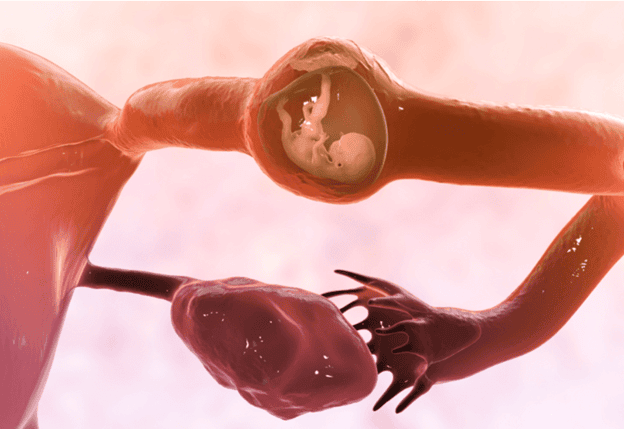

حاملگی خارج رحم ،Ectopic Pregnancy چیست؟

بارداری خارج از رحم زمانی اتفاق می افتد که یک تخمک بارور شده در خارج از رحم رشد کند. تقریباً همه حاملگی های خارج از رحم یعنی بیش از 90٪ در لوله فالوپ یا همان لوله رحمی رخ می دهد. همانطور که بارداری رشد می کند، می تواند باعث ترکیدن لوله (پارگی) شود. پارگی می تواند باعث خونریزی داخلی شدید شود و این شرایط یک اورژانس تهدید کننده حیات است که نیاز به مداخله جراحی فوری دارد.

محلهای مختلف حاملگی خارج از رحم: